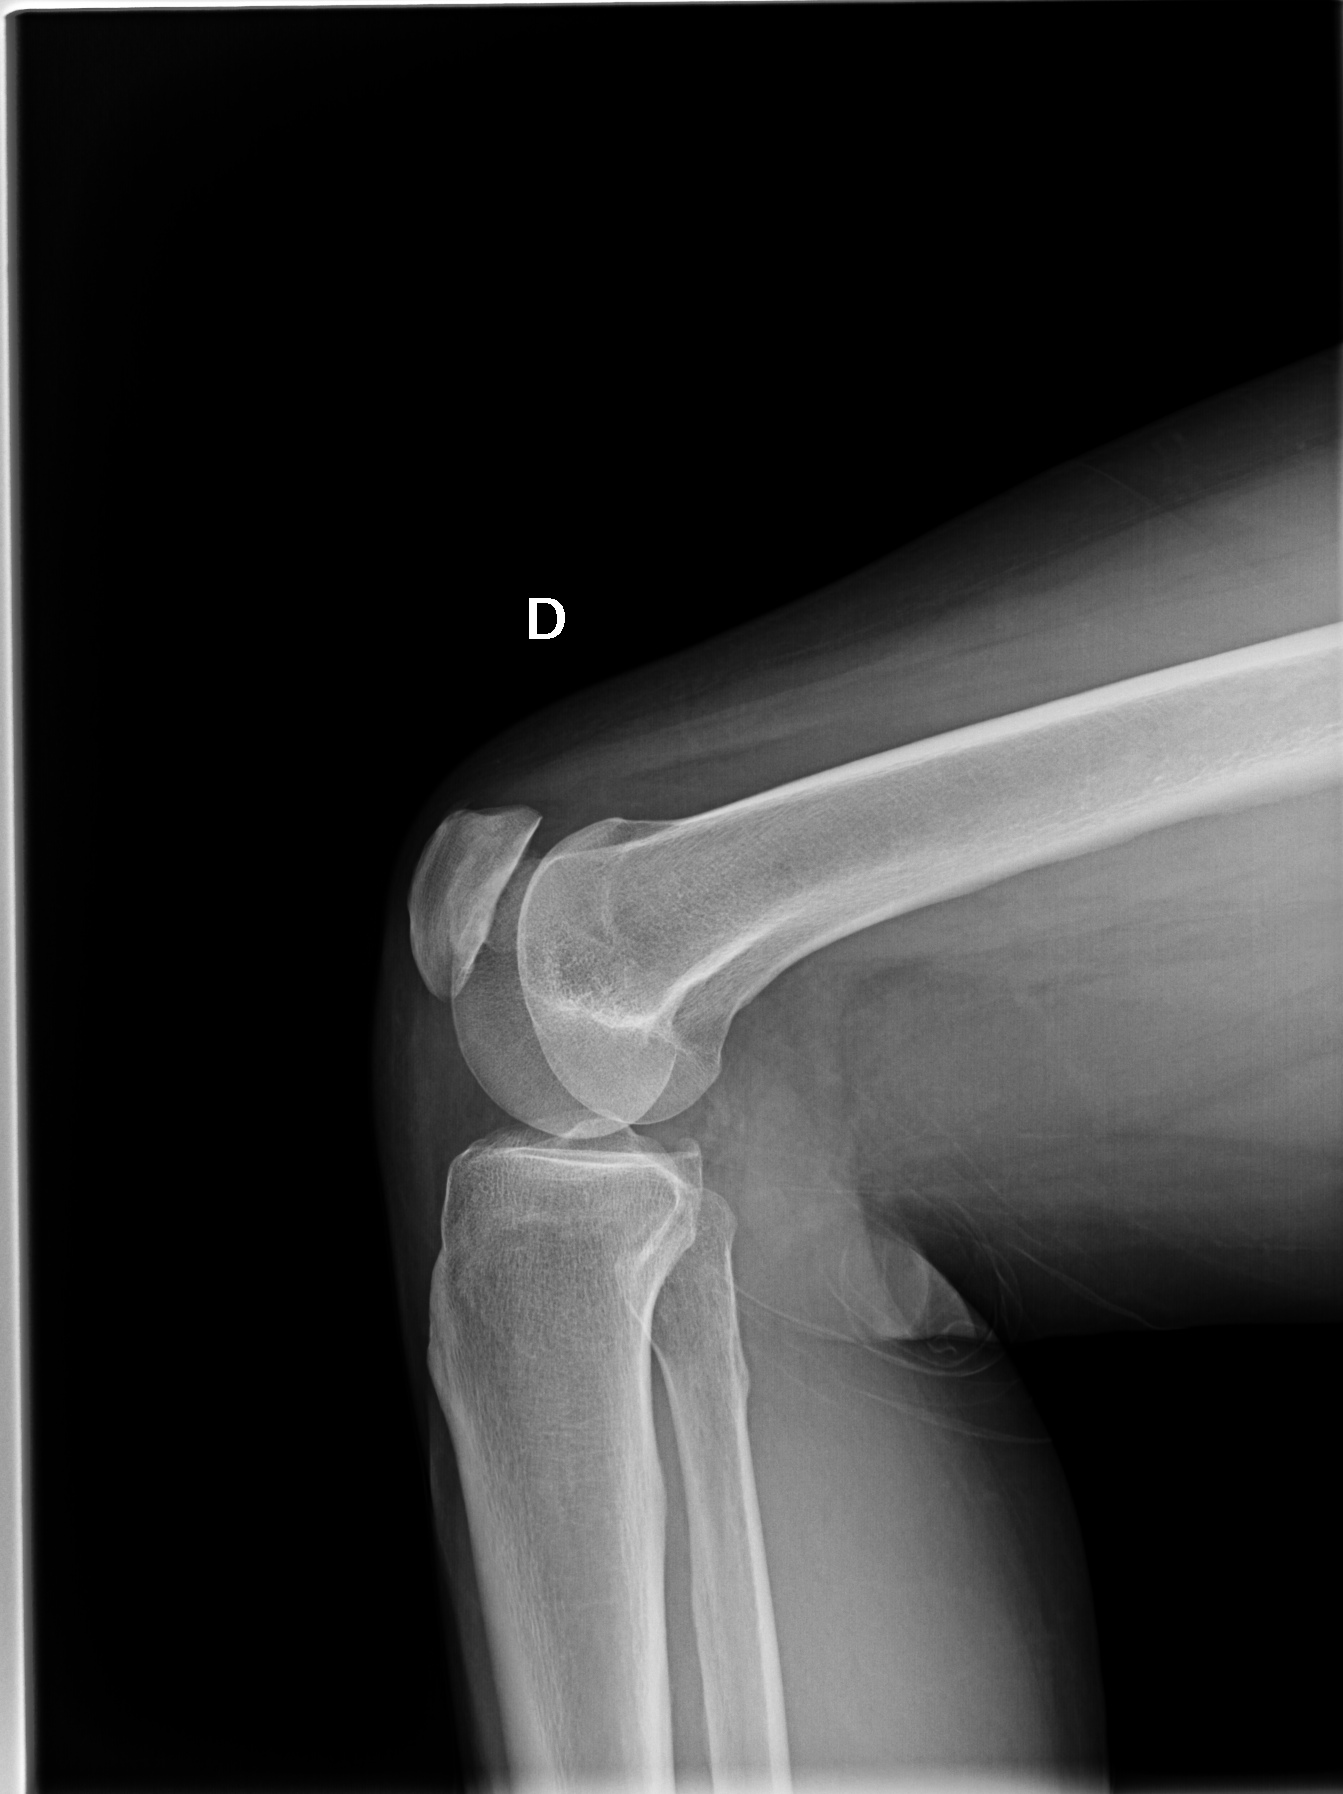

Mujer de 52 años con dolor de rodilla derecha, sin traumatismo, aunque refiere que en el útlimo mes ha comenzado clases de fitness en el gimnasio.

Se procedió a ralizar radiografía de rodilla AP, lateral y axial de rótula.

En la placa AP se aprecia una solución de continuidad en el tercio lateral de la patela derecha. La línea interarticular entre fémur y tibia está conservada.

Estos hallazgos sugieren el diagnóstico de una Rotula Bipartita, tipo II.